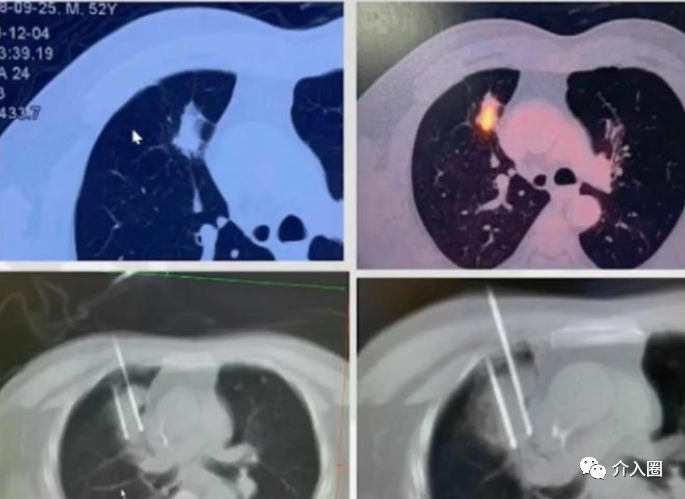

肺腺癌應用實例(來源:康博刀官方資料)

患者信息:女性,64歲,病灶位于右肺上葉前段,呈分葉狀,牽拉臨近胸膜,病灶大小為3.4x3.0x2.7cm,臨床診斷為肺腺癌

治療方案及過程:給予CT引導下冷凍消融治療術

治療結果:術后6個月復查病灶完全壞死

▲圖2 術前

▲圖3 術中冷凍消融治療

▲圖4 術后6個月復查